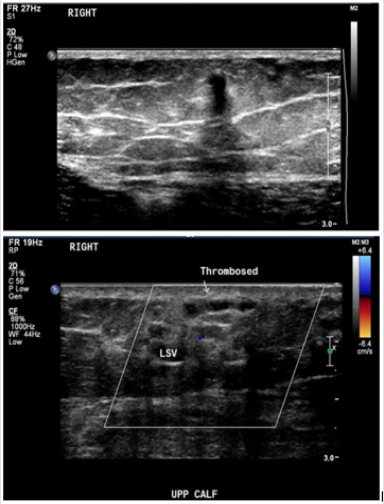

This was followed by accessing the superficial dilated tributary of the GSV within the calf from the most cranial access point using a microcatheter. The two areas of communication of this vessel with the deep veins were occluded using 2 mm x 14 cm micro coils (Figure 2c). Due to tortuosity, the actual large draining vein within the subcutaneous tissues of the calf could not be accessed by an endovascular approach. The vein was directly punctured percutaneously and was obliterated using STS foam (Figure 2d). A follow-up ultrasound scan (USS) performed 24 hours later showed thrombosis of the entire length of the GSV along and it is superficial tributary within the subcutaneous fat plane of the calf. No evidence of perfusion noted within the calf venous malformations (Figure 3). The deep veins of the right lower limb remained patent. The patient was given subcutaneous heparin to prevent deep vein thrombosis and oral NSAID for one week to attenuate the effect of thrombo-phlebitis and was subsequently discharged 24 hours later. Ultrasound follow up of the calf vm at 2 weeks and 3 months showed no flow within the venous anomaly and the GSV remained occluded to the ankle. The patient’s symptoms were much improved at the 2 follow-up time points and her lower leg varicosities had shrunken in size. Subjectively, she had experienced minimal postoperative pain (1/10) and no inflammation. Her rVCSS was 8 and 6 at 2 weeks and 3 months, respectively.